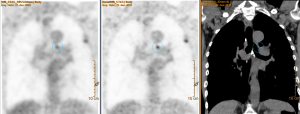

Évaluation métabolique d’une lésion sous-pleurale suspecte chez un fumeur.

Fixation bien individualisable d’un ganglion nettement infra-centimétrique.

Ça ne le rend pas pathologique pour autant, mais ça augure tout de même d’une sensibilité accrue de cette technique

Sur un Vereos.

On a commencé il y a 2 semaines et on se pose des questions tous les jours sur ces nouvelles lésions.

On a des situations paradoxales où l’on décrit des apparitions/individualisations/augmentations de foyers lors des comparaisons… et où à la fin on conclut à la stabilité parce qu’on pense que c’est juste un artéfact technologique et pas une authentique évolution de la maladie.

Du coup, on fait même en plus une reconstruction systématique en 4 mm pour dégrader l’image native et la faire ressembler aux « anciens » TEP !!